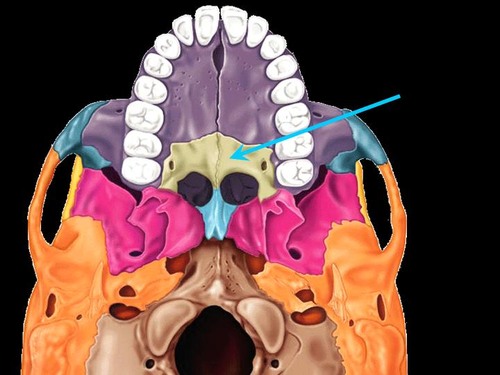

palatine process

zygomatic bone (inferior)

sphenoid bone (inferior)

vomer (inferior)

mandibular fossa

palatine bone